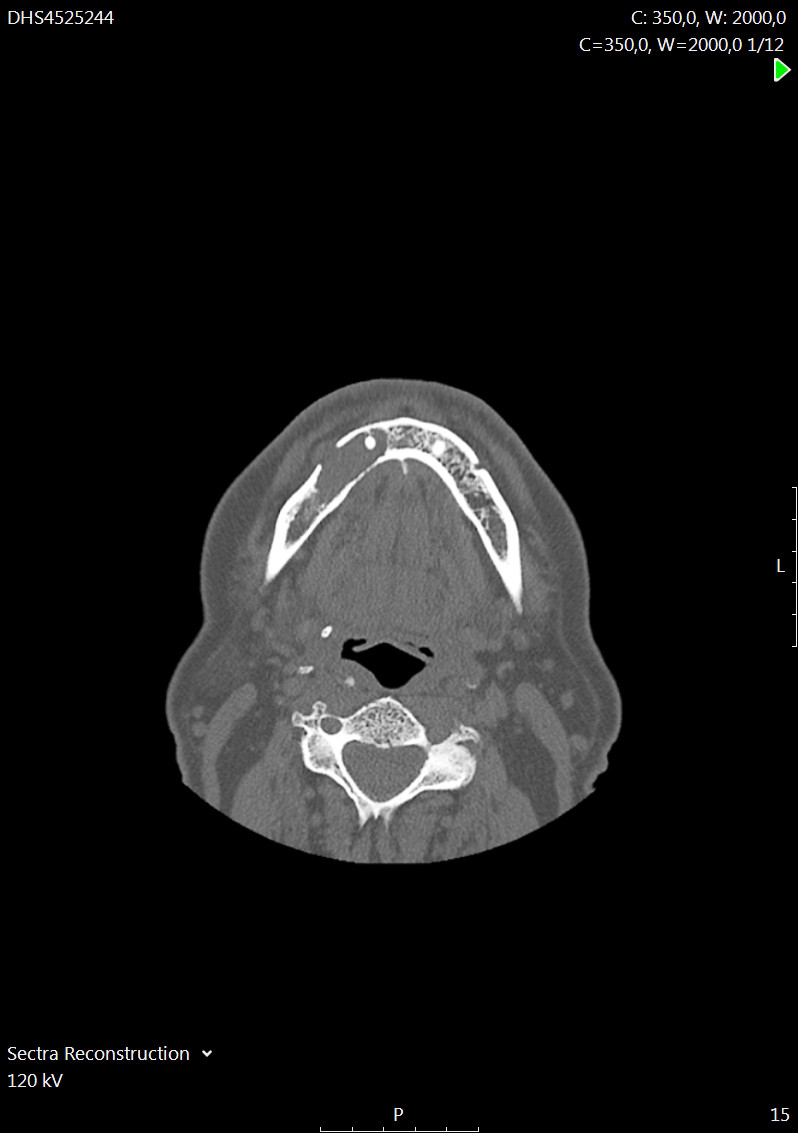

Symptomet ga mistanke om lokal påvirkning av nervus mentalis, som gir sensibilitetsutfall på haken (figur 1) (1). Pasienten ble henvist til poliklinisk CT av ansiktsskjelettet, der man så en lytisk prosess i høyre mandibula, som protruderte gjennom en utvidet foramen mentale (figur 2). Jevne kortikalkonturer uten omkringliggende fettvevsreaksjon ga primært mistanke om tumor. Abscess kunne ikke helt utelukkes, da tannrotinfeksjoner kan ha lignende utseende. Disse infeksjonene gir imidlertid oftest mindre periapikale abscesser.